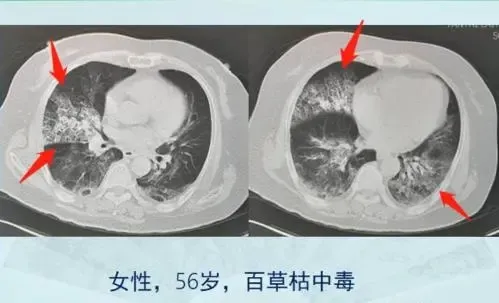

百草枯的毒性发作是循序渐进的 , 一开始没有什么感觉 , 接着消化道开始灼热 , 肚子疼痛难忍 , 损伤最严重的是肺 , 会慢慢纤维化 , 呼吸困难 , 身体开始缺氧、酸碱、水电解质紊乱 , 最终死于多器官功能障碍综合征 , 活活憋死 。

?百草枯导致的肺损伤 图源网络